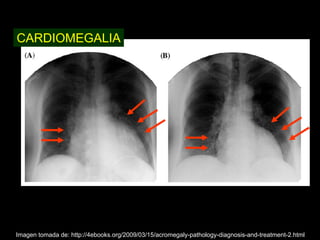

Este documento describe la acromegalia, una condición causada por un exceso de hormona de crecimiento producida por la hipófisis. Provoca un crecimiento anormal de las extremidades, la cara y los órganos internos. Sus síntomas incluyen prominencia de la mandíbula, las manos y los pies, así como engrosamiento de la piel y huesos. Generalmente se debe a un adenoma de la hipófisis y su diagnóstico se realiza mediante pruebas de sangre y resonancia magnética.